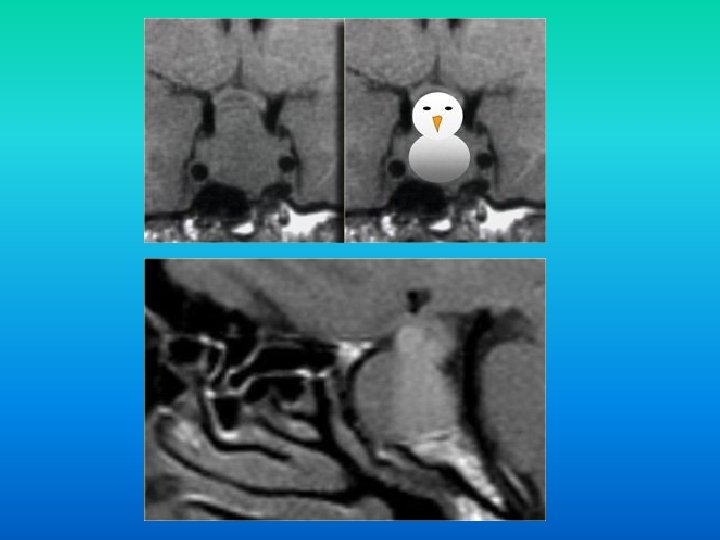

Macroadenomul Hipofizar: Adenom cu diametru >10 mm. n Deseori prezinta arii de necroza si hemoragii. n Initial extind sella turcica, apoi se extind supraselar, compresind chiasma optica sau alte structuri, cu manifestari clinice corespunzatoare. n

Macroadenomul Hipofizar: n Din cauza prezentei diafragmei macroadenoamele au o configuratie tipica de om de zapada. n Diagnostic diferential de meningiom. ♠ Suplimentar numai macroadenoamele extind sella turcica.

Extindere in sinusul cavernos: n Diagnostic diferential: meningioamele tind sa comprime artera (arterele) carotida, iar adenoamele nu (tesut practic lipsit de stroma).